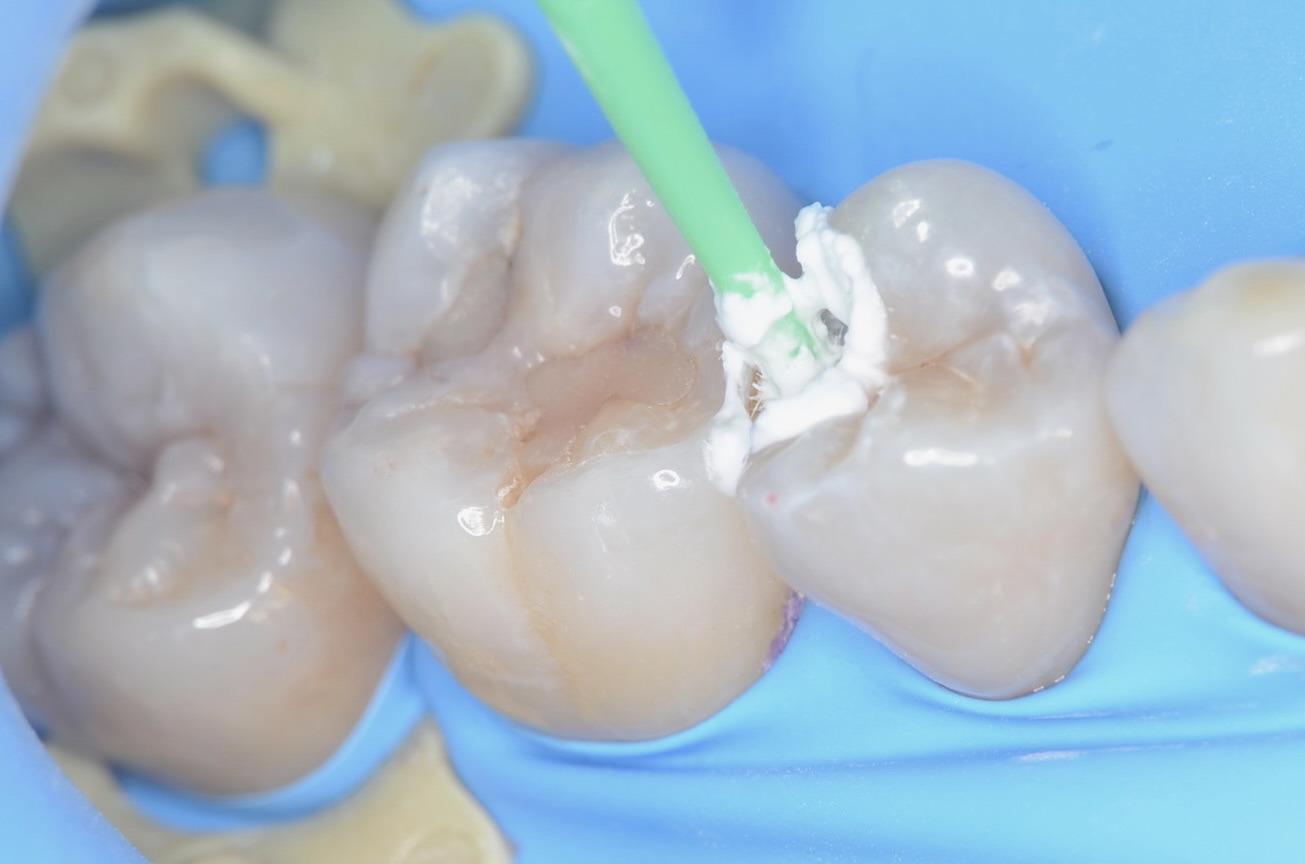

ダイレクトボンディング

フロワブルレジンを用いて、その表面張力を利用して滑らかで段差のないレジン充填を実現させます。 セパレーターで歯間離開させながら光を当てながらレジンを硬化させる3Dプリンターテクニックを用いて治療しました。 -

歯と歯の間の充填終了

充填後、フロスを歯間部に通して引っ掛かりや適切な接触強さを確認します。 -